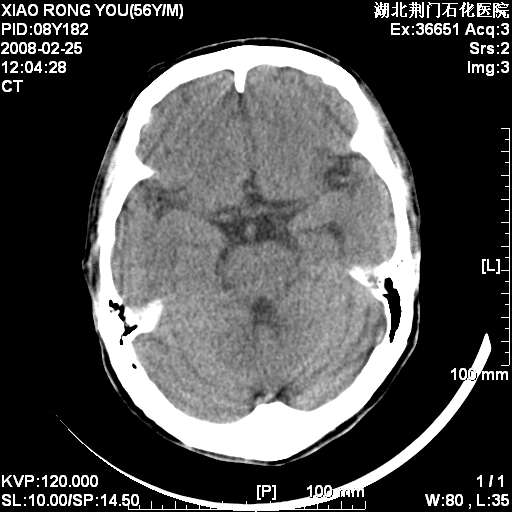

1月后复查

转移瘤,前后对比可发现复查片左顶叶出现一低密度灶

病变范围在一个多月时间增大,且密度不均周围有税种,并且多发!考虑转移瘤!

左枕/顶叶出现新病灶,转移瘤